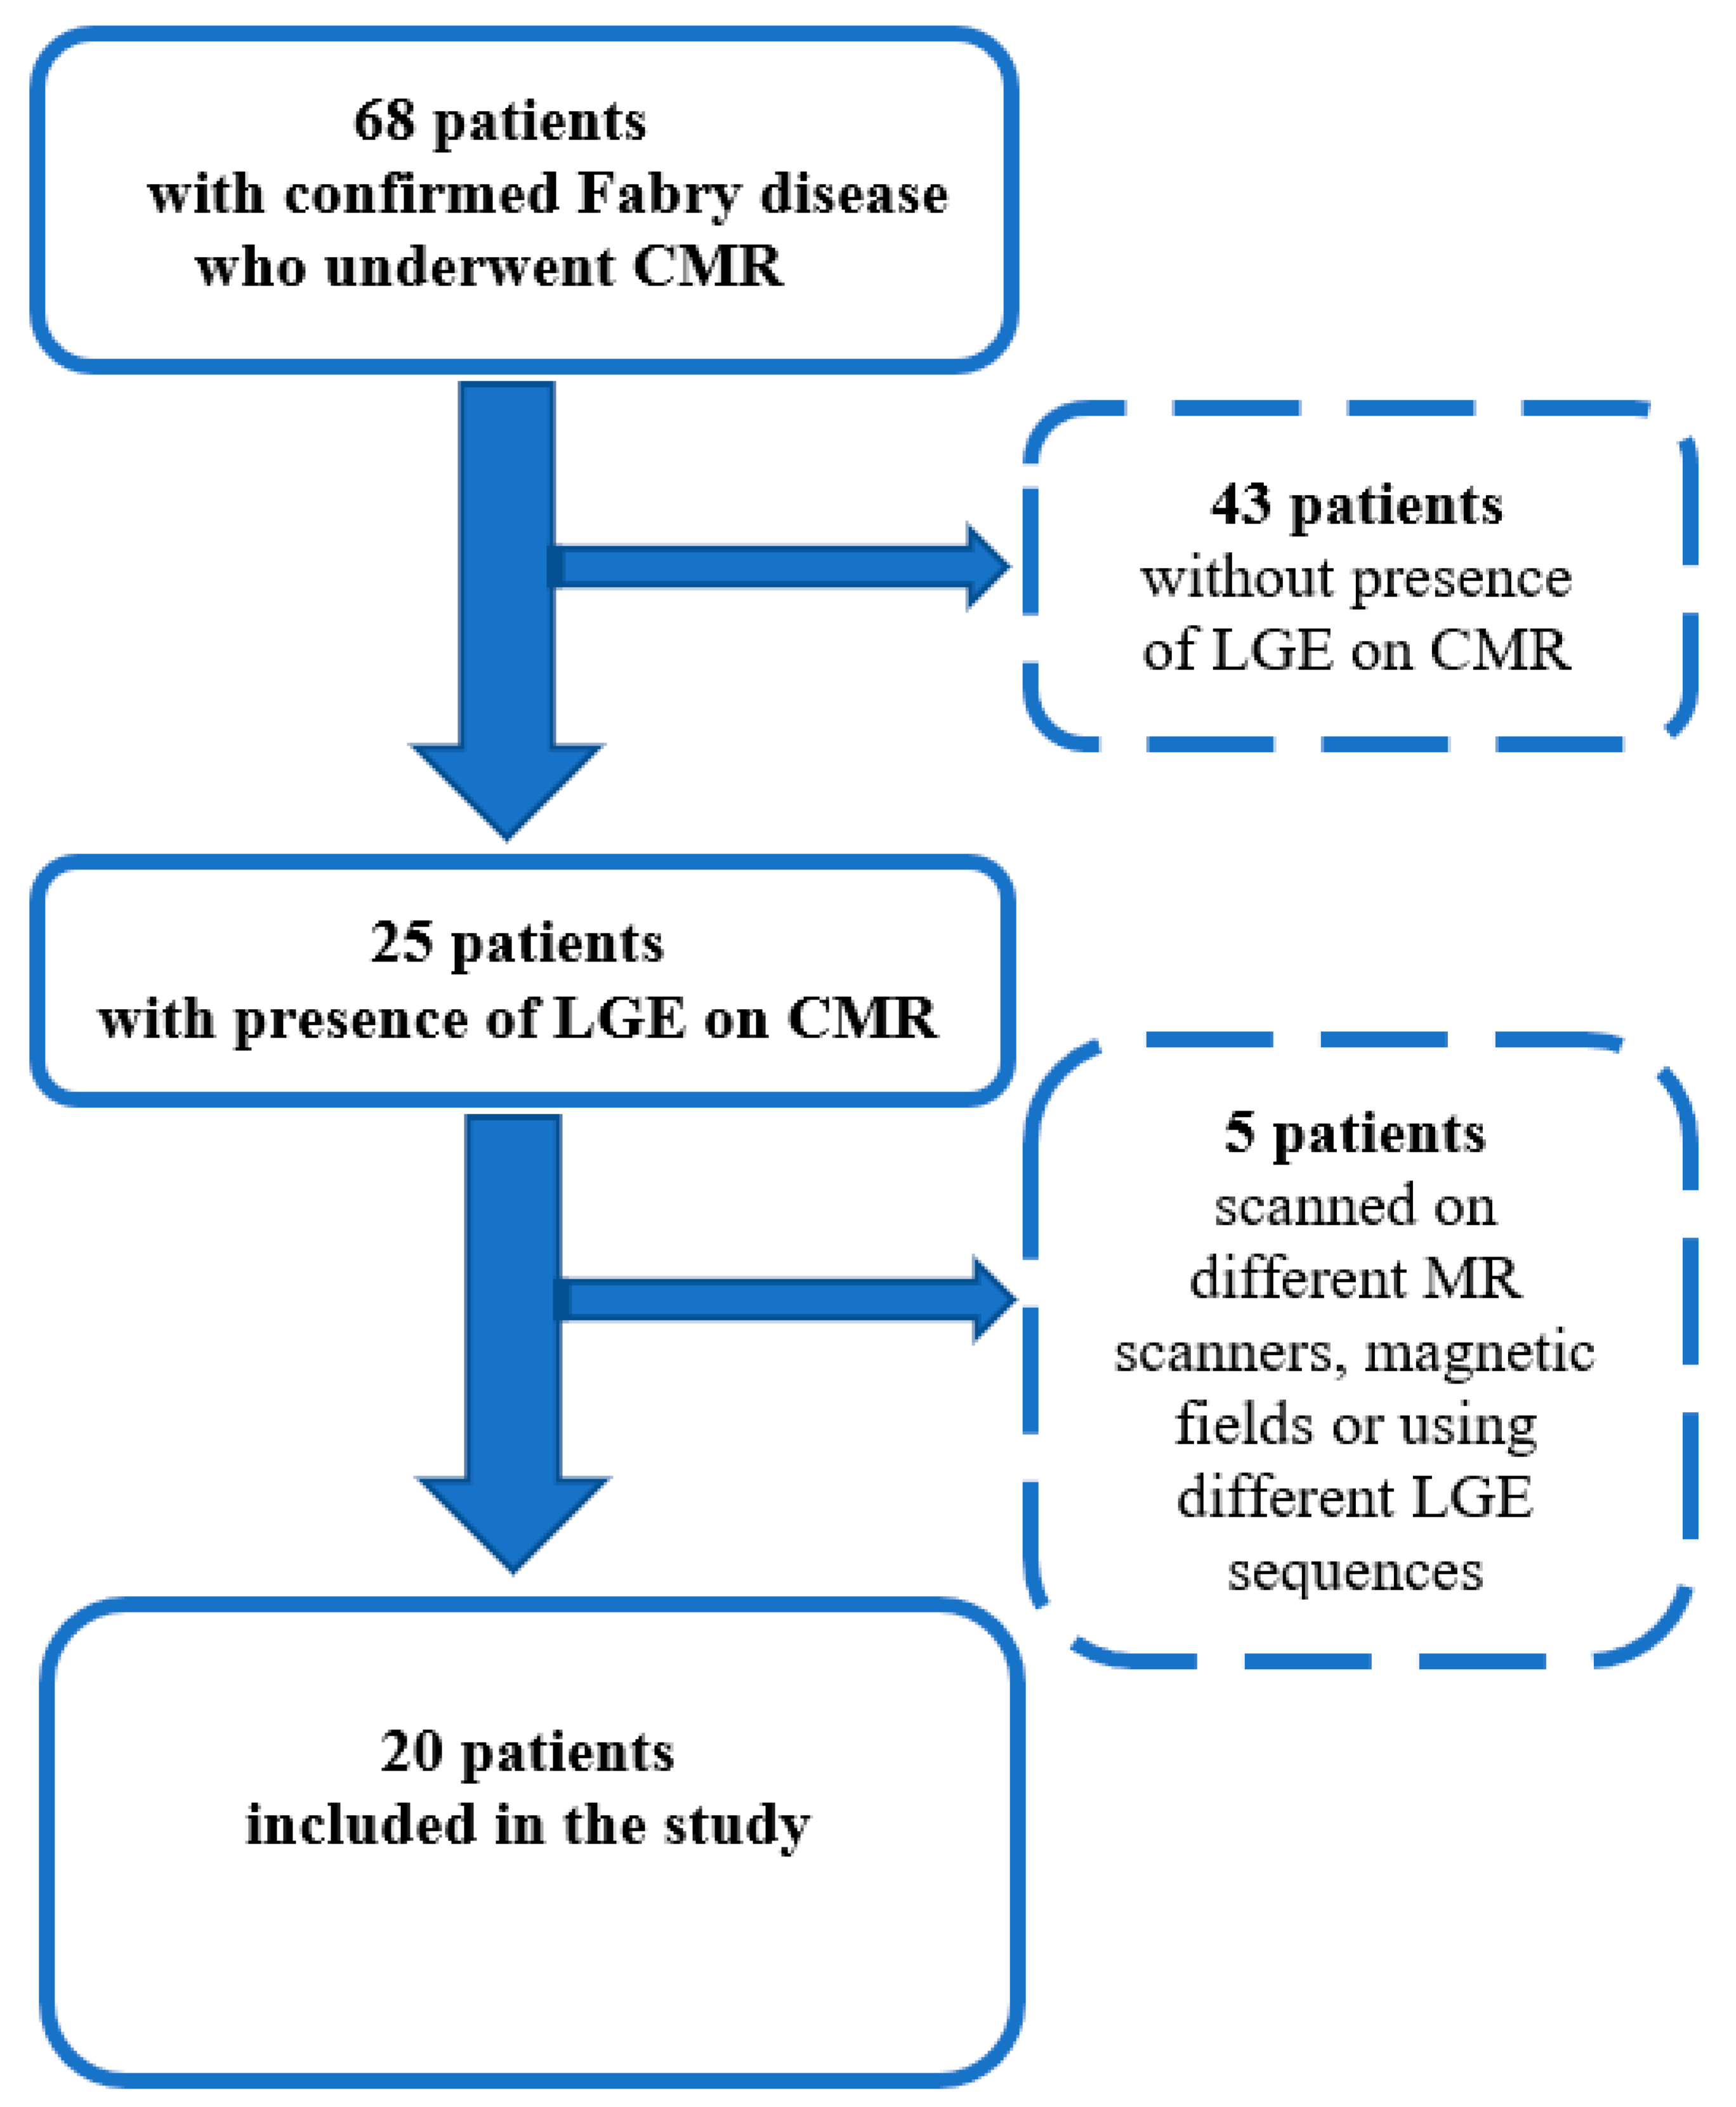

2.1. Study Population